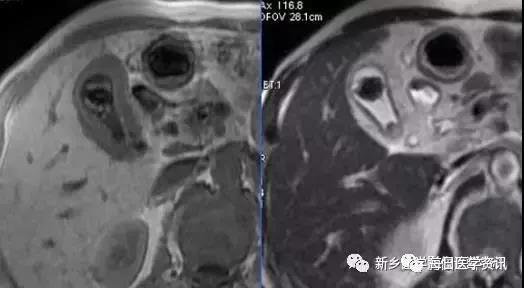

胆囊腺肌症

胆囊壁增厚+假憩室形成(胆囊壁平滑肌增生相关的罗-阿氏窦)